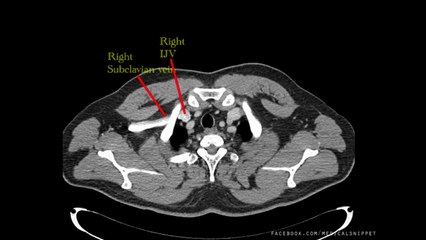

Scientists have proposed the idea that brain fog in sufferers of long Covid is caused by leaky blood vessels.